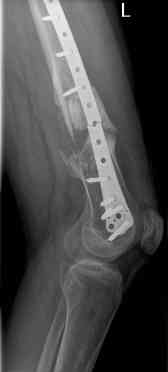

16 yr old boy, high energy motorcycle trauma trauma in July 2005 with:

- hip dislocation + acetabular fracture L

- distal femoral fracture L

- tibial shaft fracture L

- metatarsal fractures L

july 05: LISS femur, LCP plate tibia, double recon. plate post. acetabulum

feb 07: retrograde nail + bone graft + BMP

nov 07: persistant non-union distal femur; other fractures healed